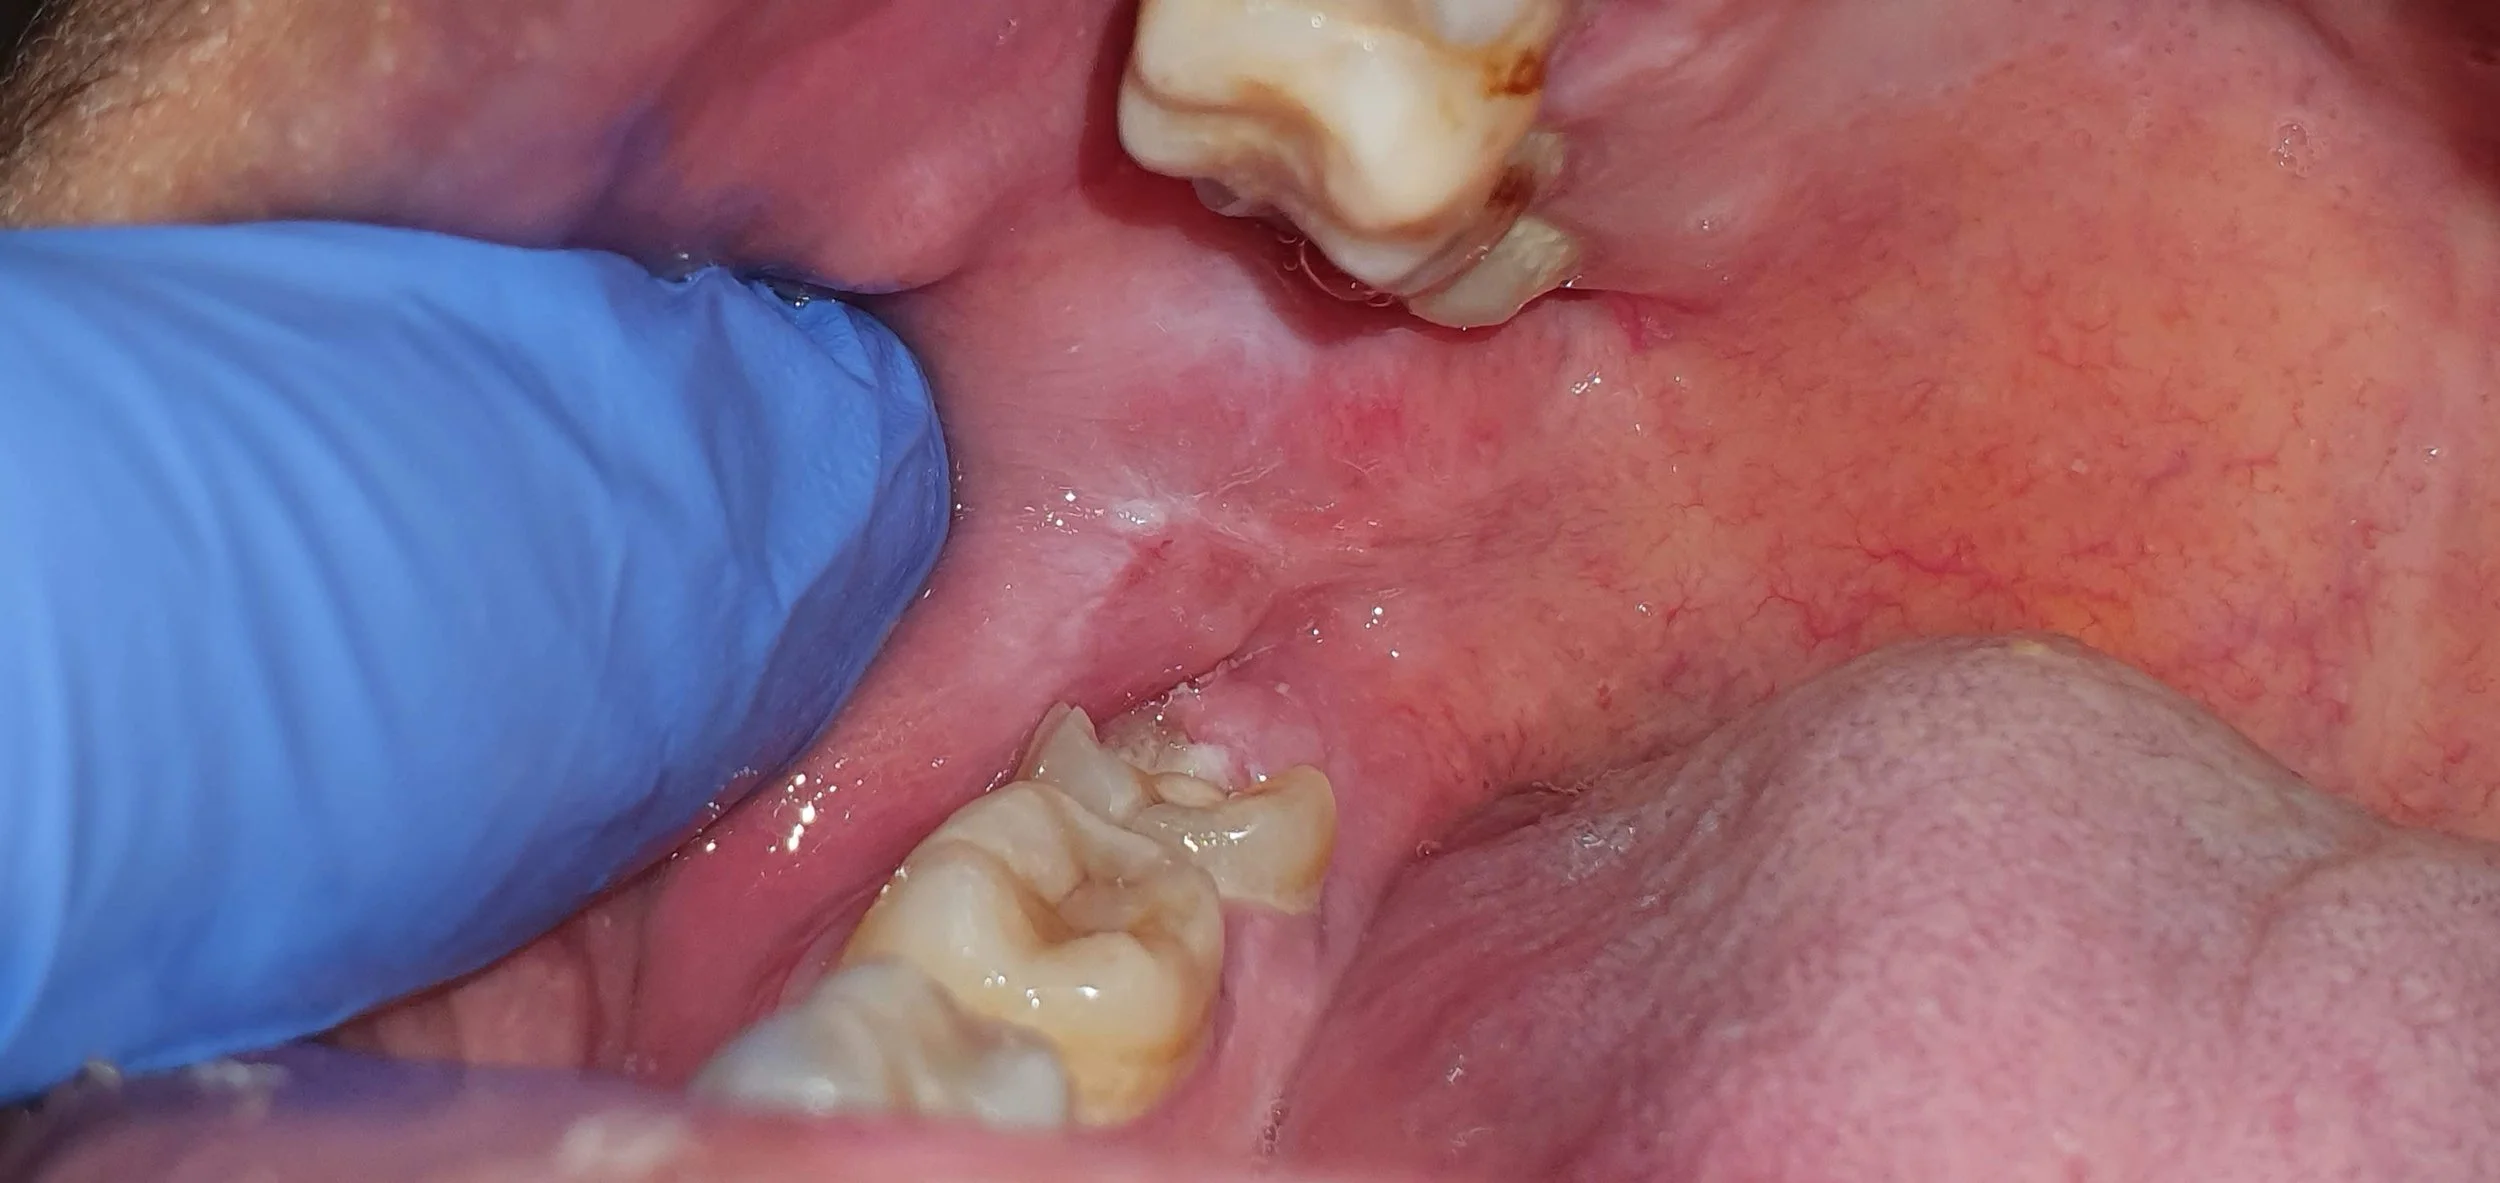

Dental

May 11th Dr Stuart Duncan local Dentist tries to cram a whole dental degree and heaps of pearls into his 2 hour session. This had lots of favourable comments made after the session was given

Dental Teaching

Dental Trauma pdf